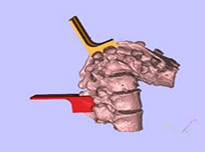

畸形的脊柱 手术方案

建模过程:

根据手术方案中的脊柱形态进行测量,定制个性化的假体和截骨导板。

需要截骨的平面

截骨导板放置位置